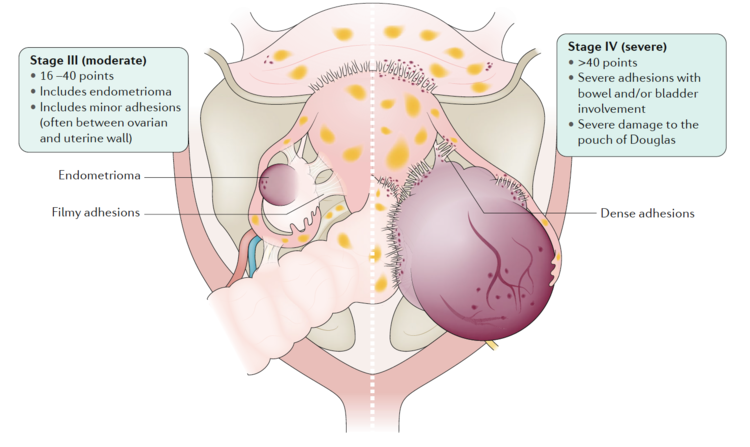

Endometriosis is a condition where endometrial-like tissue (membrane that lines the uterus) forms outside of the uterus. It is mainly found within the pelvic peritoneum (tissue that lines the pelvis), in the ligaments supporting the womb and the ovaries, and also less commonly in the appendix, bowel, or bladder. On rare occasions, we can also find endometriosis in the abdominal wall, belly button, liver, diaphragm, and lungs. Endometriosis is staged between the mildest form (level 1) to the severest form (level 4).

Stage 1-2 Pelvic endometriosis. Endometriosis, Nature Reviews Disease Primer, 2018, Vol 4(1) pp.9

Stage 3-4 Pelvic endometriosis. Endometriosis, Nature Reviews Disease Primer, 2018, Vol 4(1) pp.9